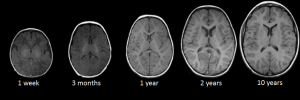

Развитие головного мозга - это динамичный процесс прогрессивных и регрессивных изменений, продолжающийся на протяжении всей жизни, ранние этапы которого являются критически важными для нормального функционирования и адаптации к окружающей среде в будущем. Патологические состояния, препятствующие таким процессам созревания, могут привести к задержке развития нервной системы во взрослом возрасте [1]. Исследования показывают, что характер изменений зависит от множества факторов, включая возраст и пол ребенка [2-5]. Процессы формирования нервной системы наиболее интенсивно происходят в течение первых 3 мес постнатального периода. К моменту достижения трехлетнего возраста завершается дифференцировка нейронов, характеризующаяся удлинением аксонов, их усиленной миелинизацией, а также увеличением количества и степени ветвления дендритов [6]. К восьми годам организация коры головного мозга соответствует коре взрослого человека [7]. Перекрестные исследования, изучающие развитие мозга у детей и подростков, демонстрируют увеличение объема белого вещества и уменьшение объема серого вещества в более позднем детском и раннем подростковом возрасте [8-10]. В зарубежной литературе описывается U-образная траектория изменения объема серого вещества коры головного мозга у детей, характеризующаяся увеличением в раннем детстве с последующим уменьшением в пубертатный период: максимально размер достигается к 16,5 годам у мальчиков и к 16,7 годам у девочек [8, 11-13]. Особенностью процесса развития головного мозга является значительное увеличение площади коры при относительно незначительном увеличении ее толщины [14]. Объем белого вещества увеличивается на протяжении всего детского и подросткового возраста с максимальными размерами в возрасте 10,5 лет у девочек и 14,5 лет у мальчиков [3, 15]. Максимальный объем мозга достигается в возрасте около 10,5 лет у девочек и 14,5 лет у мальчиков [3]. У взрослых мужчин объем мозга примерно на 7-10% больше, чем у женщин [2-4].

Кора височных долей, особенно их задние отделы, является важным гетеромодальным ассоциативным участком мозга, интегрирующим различные виды информации: зрительную, слуховую, тактильную. Верхняя височная борозда и прилегающие области участвуют в интеграции аудиовизуальной информации. Средняя и нижняя височные извилины вовлечены в процессы зрительного восприятия и распознавания объектов. Гиппокамп, расположенный в медиальной части височной доли, играет ключевую роль в консолидации памяти [16-18]. Гиппокампы претерпевают резкий рост в период до 2 лет, а затем продолжают медленно увеличиваться в объеме даже после начала полового созревания [19].

На основании разделения исследуемых на 2 возрастные группы (0-7 и 7-18 лет), соответствующие критическим периодам созревания центральной нервной системы, нами выявлены характерные изменения в морфометрических параметрах структур височных долей. Темп развития нервной системы особенно высокий в течение первых 3 мес жизни.

Дифференцировка нервных клеток достигается к 3 годам, а к 8 годам кора головного мозга по строению похожа на кору взрослого человека.